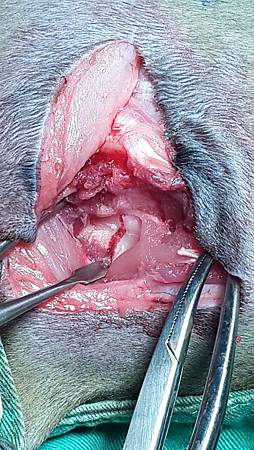

2014-12-22 15.24.40.jpg

骨折處